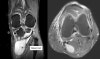

MRI가 필요하지는 않지만, 낭종의 위치와 낭종액의 유형, 다른 관절 속 병변 존재를 알 수 있습니다.

드물게는 synovial sarcoma 등의 악성 종양을 감별해야 하는 경우도 있습니다.

MRI : 베이커 낭종(슬와낭종, Baker's cyst, Popliteal cyst)